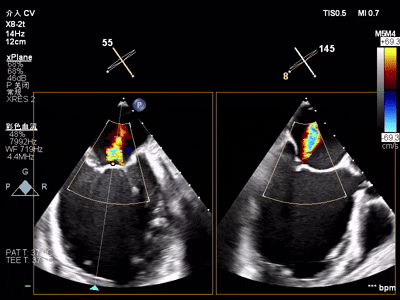

术前术后反流对比

【术后一周复查心超提示】二尖瓣钳夹术后,二尖瓣反流(轻度),夹合器固定,瓣口呈双孔结构,内外侧孔分别见微量反流,反流束VC分别 0.15cm、0.18cm,估测有效瓣口面积约2.5c㎡,舒张期瓣口前向最大血流速度 1.2m/s,平均压差3mmHg,左室射血分数(EF)值提升至35%,心功能显著改善。目前患者已顺利康复出院。